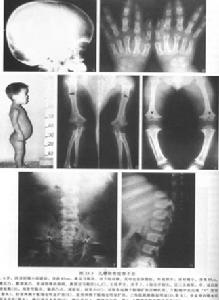

軟骨發育異常侏儒症(一)侏儒本病是侏儒的最常見原因。胎兒娩出時即可見其身體長度正常而肢體較短,這種差別以後逐漸明顯,肢體近端如肱骨及股骨比遠端骨更短,患兒脂肪臃腫。至發成熟,平均身高男性為131±5.6cm,女性為124±5.9cm。文獻上有97cm和104cm的報告。患兒身體的中點在臍以上,有時甚至在胸骨下端。兩手只能碰到股骨下粗隆的下方,而不象正常人那樣可以達到大腿下1/3。因為肢體短,在下肢伸直位時,面部可碰到足趾。

(二)頭顱增大有的病人有輕度腦積水,穹隆及前額突出,馬鞍型鼻樑,扁平鼻、厚嘴唇、舌伸出(在嬰兒)。

軟骨發育異常(四)胸腔扁而小,肋骨異常的短。

(五)手指粗而短,分開,常可見4、5指為一組,2、3指為一組,拇指為一組,似“三叉戟”。有的病人的伸肘動作輕度受限。

(六)下肢呈弓形,走路有滾動步態(rolling)。

X線表現①顱蓋大,前額突出,頂骨及枕骨亦較隆突,但顱底短小,枕大孔變小而呈漏斗型,其直徑可能只有正常人的1/2。如伴發腦積水側腦室擴張。②長骨變短,骨幹厚,髓腔變小,骨骺可呈碎裂或不齊整。在膝關節部位,常見骨端呈“V”形分開,而骨骺的骨化中心正好嵌入這V形切跡之中。由於骨化中心靠近骨幹,使關節間隙有增寬的感覺。下肢弓形,腓骨長於脛骨,上肢尺骨長於橈骨。③椎體厚度減少,但脊柱全長的減少要比四肢長度的減少相對少很多。自第一腰椎至第五腰椎,椎弓間距離逐漸變小。脊髓造影可見椎管狹小,有多處椎間盤後突。④骨盆狹窄,骼骨扁而圓,各個徑均小,髖臼向後移,接近坐骨切跡,有髖內翻,髖臼與股骨頭大小不對稱。肋骨短,胸骨寬而厚。肩胛角不銳利,肩胛盂淺而小。